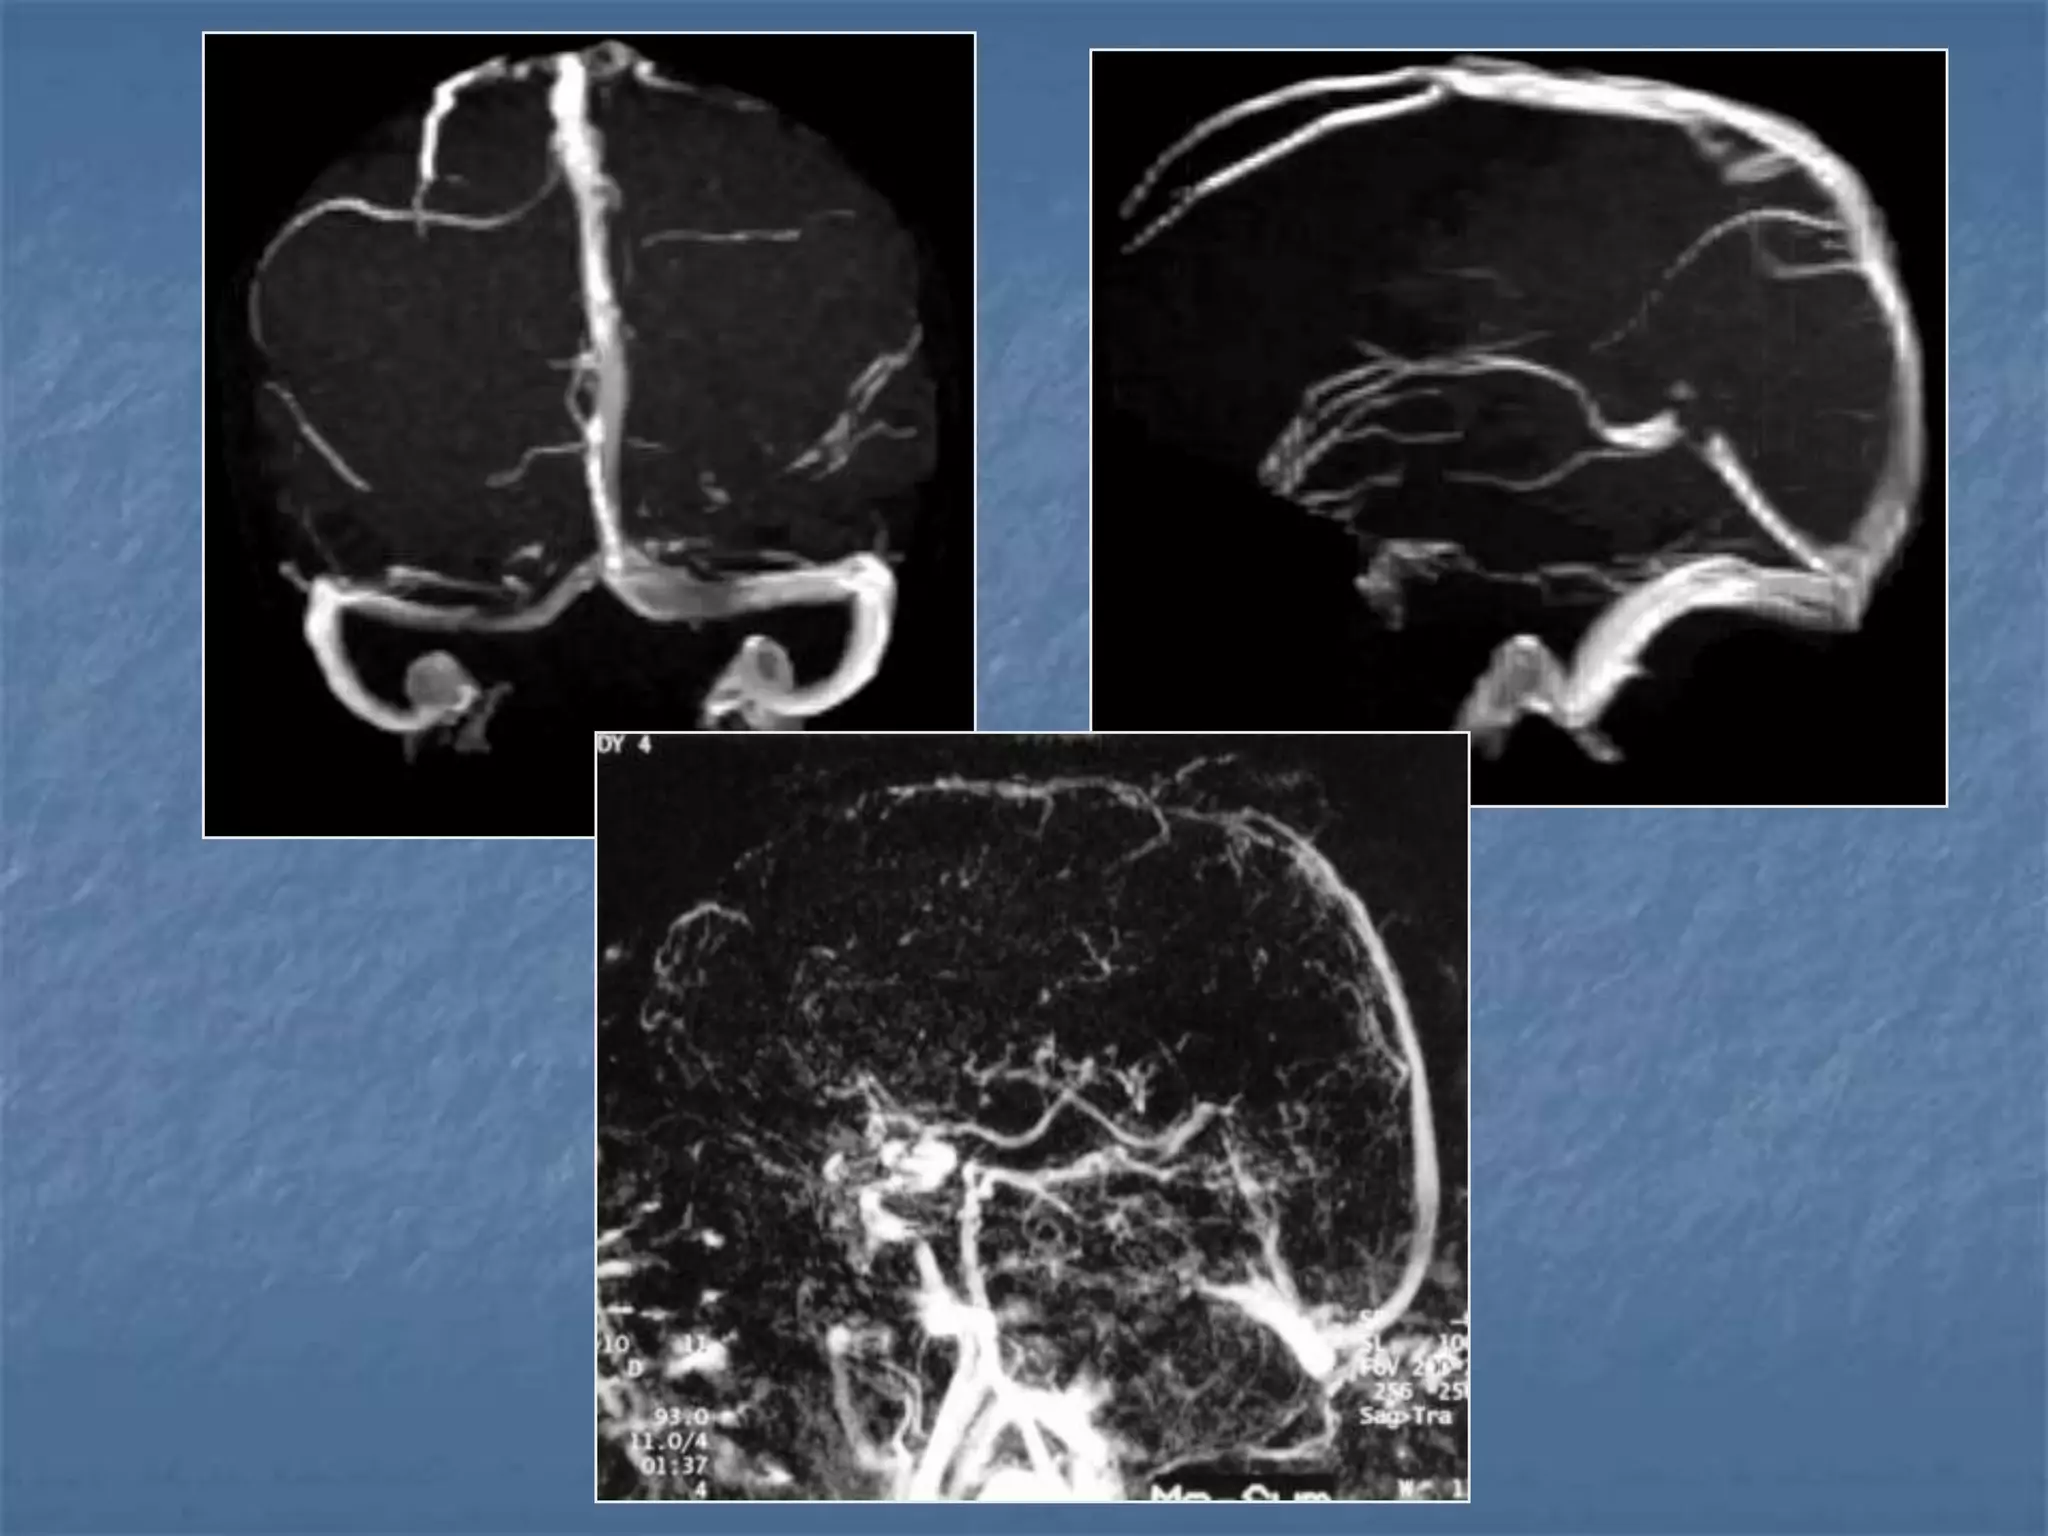

CT Venography

Venous Sinus Thrombosiswith Venous Infarct  Clinical symptoms – head ache, seizures  Pathology is due to decrease in perfusion pressure as the venous pressures elevate due to occlusion.  Predisposing conditions are dehydration, infection, polycythemia, sickle cell disease, hypercoagulable states, peripartum, OCP poisoning. Imaging findings  Unilateral / bilateral parenchymal hypodensities  Not limited to an arterial territory  May be associated with hemorrhage  Signs: Delta sign, Enhancement of walls of sinus than their contents.

Imaging findings

 Unilateral / bilateral parenchymal hypodensities

 Not limited to an arterial territory

 May be associated with hemorrhage

 Signs: Delta sign, Enhancement of walls of sinus than

their contents.